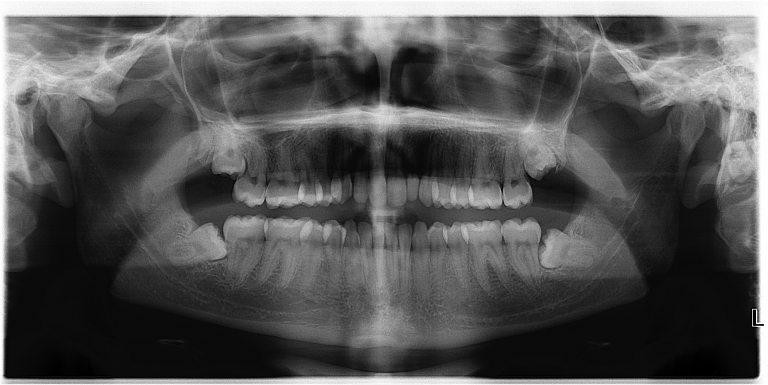

4. Răng khôn

![]() |

Răng khôn không hề "khôn" như tên gọi của nó (Ảnh: Hack Spirit) |

Thời tiền sử, những chiếc răng khôn được sử dụng để nghiền thức ăn giúp cho con người dễ tiêu hóa hơn. Tuy nhiên ngày nay, việc con người chuyển sang ăn những thực phẩm được nấy chín, cùng với đó là việc kết hợp dao nĩa khiến cho những chiếc răng khôn này trở nên vô tác dụng. Đáng ghét hơn, những chiếc răng khôn này còn khiến cho chúng ta bị đau, làm xô lệch hàm răng khi chúng mọc lên.